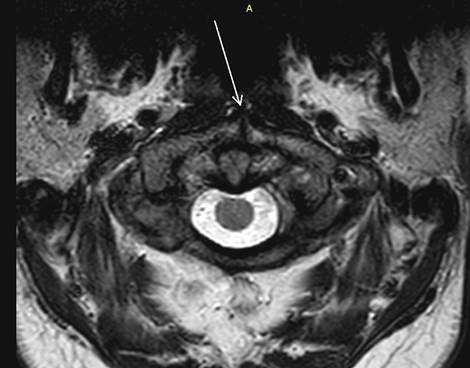

Результаты исследования и их обсуждение. Из 2857 мр-исследований шейного отдела позвоночника незаращение передней дужки атланта (рис. 4) было выявлено в 6 случаях (0,21±0,09%). Средний возраст обследуемых составил 43±5,4 года, возрастной диапазон выявленных случаев расщепления атланта составил от 34 до 48 лет. Из них мужчин было 1 (16,7%), женщин – 10 (83,3%). Диастаз расщелины варьировал от 0,3 до 2,1 мм, М = 1,4±0,7 мм.

Рис. 4. Аксиальный срез (Т2ВИ, стрелкой указан split atlas)